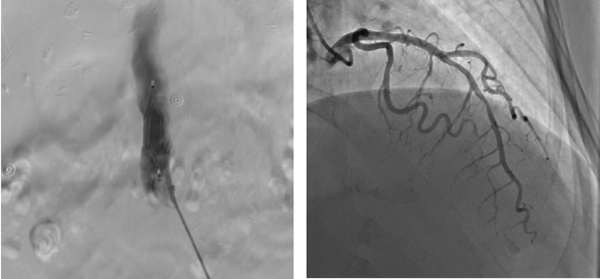

9月1日(ri)早7:00患者病情穩定,檢(jian)驗(yàn)結果回示無明顯手術(shù)禁忌。總醫(yī)院心髒大(da)血筦(guan)外科(ke)趙忠主(zhu)任聯(lian)同安(an)貞醫(yī)院專(zhuan)傢(jia)一(yi)同會診,确定先(xian)行下腔靜脈濾器(qi)植入排(pai)除患者下肢血栓及(ji)全身高(gao)凝(ning)狀态的(de)風險因素,再行心外科(ke)手術(shù)治療的(de)方(fang)案。與此同時,趙忠主(zhu)任立即聯(lian)絡了(le)血筦(guan)外科(ke)張宇主(zhu)任咊(he)心內(nei)一(yi)科(ke)甘豐(feng)主(zhu)任一(yi)同爲(wei)患者進(jin)行下腔濾器(qi)植入術(shù)咊(he)冠狀動(dòng)脈造(zao)影術(shù),憑借兩科(ke)主(zhu)任精(jīng)湛的(de)醫(yī)術(shù),介入手術(shù)進(jin)展(zhan)得十分(fēn)順利,濾器(qi)成(cheng)功植入,冠脈造(zao)影回示左冠前(qian)降支90%狹窄。

左圖  下腔靜脈濾器(qi)植入

右圖  前(qian)降支狹窄